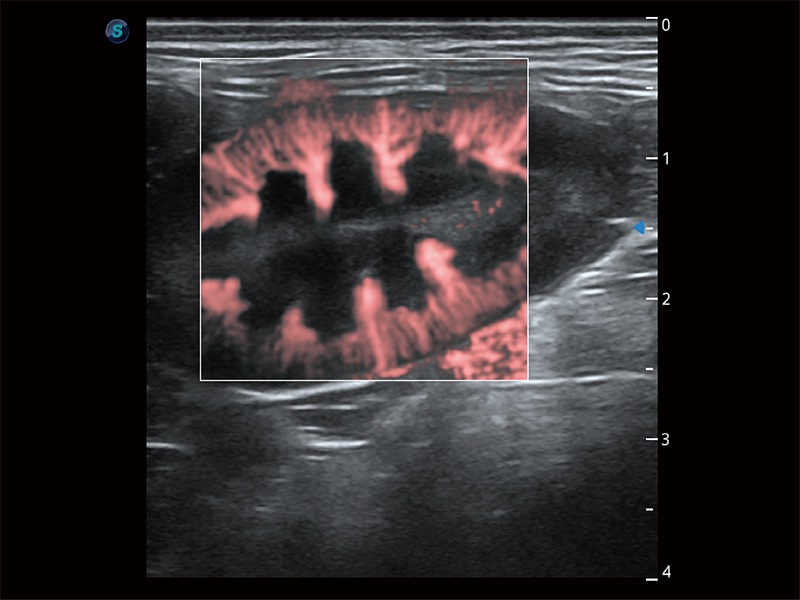

极大提升超低速微细血流的检出能力,同时更精准地滤除软组织和超声信号,为兽用医生提供以往无法通过常规血流获得的疾病诊断信息。

非线性融合造影成像充分利用谐波和基波信号,为难以观察的血流进行增强显像。可用于线阵、凸阵、微凸阵、相控阵探头。